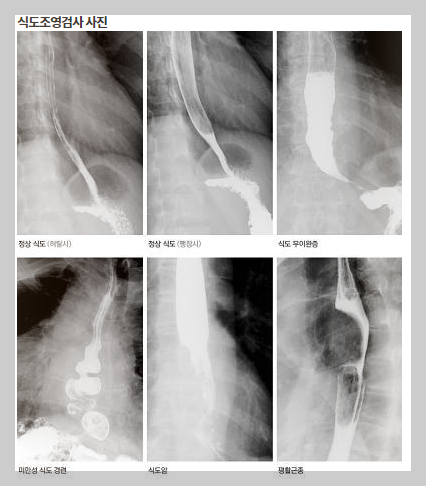

식도조영술 검사 목적과 주의사항

영상의학과에서 실시하는 식도조영술 검사의 목적과 검사 적응증, 식도 조영술 검사 전처치, 검사 후처치, 주의사항 등에 대해서 알아보았습니다.

식도조영술은 X선에 불투명한 조영제를 이용하여 식도의 구조와 기능을 관찰하는 검사입니다.

- 식도의 기형이나 협착: 선천적인 기형이나 염증, 종양 등으로 인한 식도 협착 여부를 확인합니다.

- 식도의 종괴: 식도암과 같은 종양의 유무 및 크기, 위치를 확인합니다.

- 식도의 연동운동 장애: 식도가 음식물을 위로 내려보내는 운동 기능에 이상이 있는지 확인합니다.

식도조영술에서는 식도의 길이, 굵기, 굴곡, 그리고 주변 기관과의 관계를 관찰합니다.